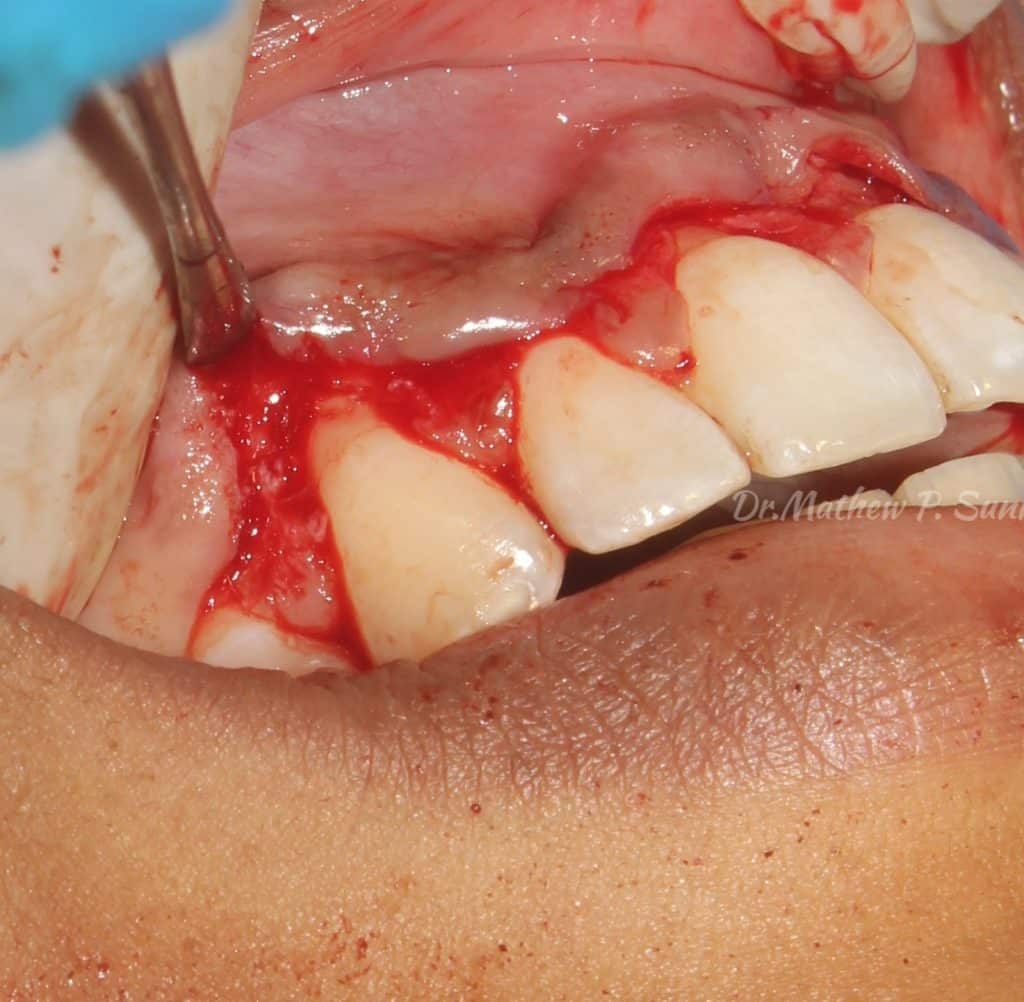

gingivectomy done initially to establish final gingival margin positions..

flap raised..

osseous recontouring done to establish 3 mm biological width..